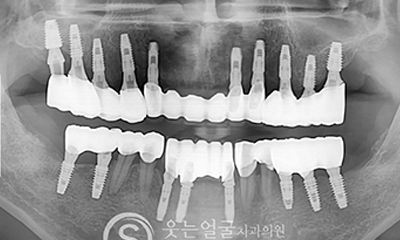

고난이도 임플란트

웃는얼굴치과는 풍부한 경험과 전문성을 바탕으로

일반적인 케이스는 물론,

고난이도의 임플란트 수술까지

안전하게 진행합니다.

뼈 이식이나 발치 즉시 식립 등 까다로운 조건에서도 정밀 진단과

체계적인 시술 시스템으로 환자 맞춤형 치료를 제공합니다.

8천여건의 다양한

임플란트 수술 케이스

다년간 축적된 8,000여 건 이상의

임플란트 수술 경험을 바탕으로,

환자 개개인의 구강 구조와

상태에 최적화된 안전하고 정확한 시술을 제공합니다.